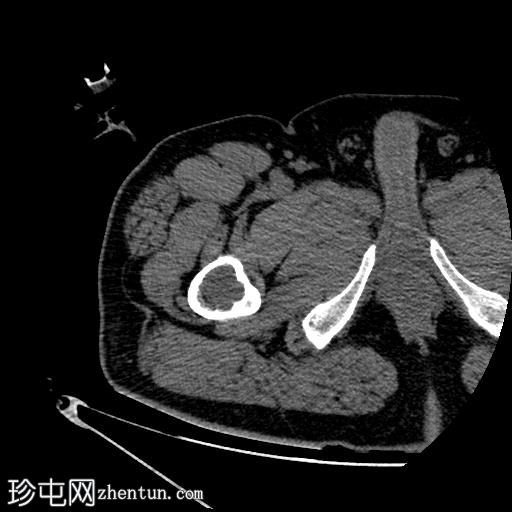

轴位

平扫

将活检针置于右股骨近端干骺端溶骨性透亮肿块中心后,从囊性病变中抽取血液。穿刺活检结果为阴性,未见骨髓浸润。因此,囊性病变的血液样本被送检进行组织病理学检查,结果显示无恶性肿瘤

根据CT影像学表现和组织病理学结果,应考虑右股骨干近端良性囊性骨病变。